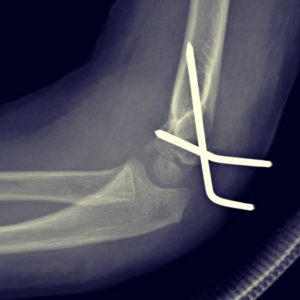

- Fracturas de codo

- Fractura de cóndilo humeral

fractura de condilo humeral